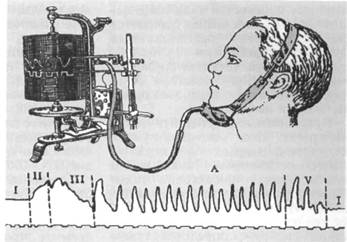

Электромиография — наиболее информативный метод определения функционального состояния мышц. Этот метод исследования заключается в регистрации биоэлектрических потенциалов, возникающих в мышцах в момент возбуждения. Исследуемая электрическая активность характеризует контрактиль-ный ответ мышцы, зависящий от особенностей ее иннервации. С помощью электромиографии изучают функциональное состояние поверхностно расположенных мышц лица

Электромиографию осуществляют с помощью специальных приборов — электромиографов различных конструкций (рис. 13.30). Результаты исследования регистрируют в виде электромиограмм (ЭМГ).

Рис. 13.30. Электромиограф «Меделек» с компьютерной системой обработки данных.